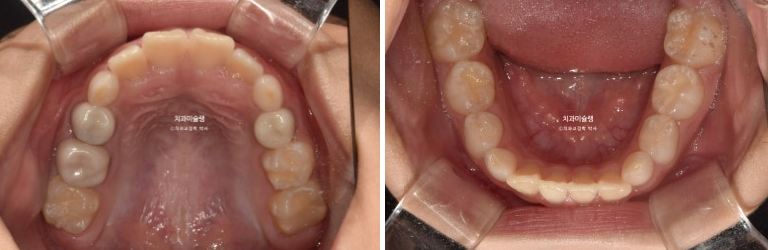

앞니 위아래 4개씩 총 8개 영구치 앞니는 약간의 삐뚤함이 있지만 큰 공간부족 없이 잘 나온 편 입니다.

첫 세트 장치는 총 46개가 나왔습니다.

24년 2월까지 4개월간 악궁확장, 영구채 나올 공간 넓히기, 앞니배열, 과개교합 개선 등을 먼저 진행 한 후 2월부터 Mandible advance 단계에 들어갑니다.